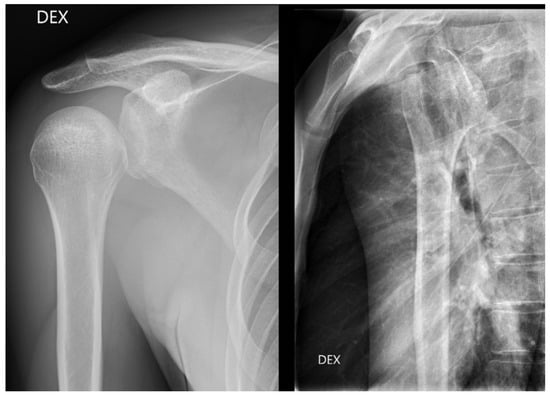

From all the missed findings in the radiographs, 70% (n = 44) were interpreted as having an impact on patient care (p = 0.02), but this did not differ between the radiology specialists and the residents. Findings missed by the radiology specialists (Figure 4 and Figure 5) affected patient care in 71% of cases and overcalls in 31% of cases. Findings missed by the residents (Figure 6) affected patient care in 69% of cases and overcalls in 47% of cases. From all the overcalls in the radiographs, 40% (n = 12) seemed to have an impact on patient care. The most common impact on patient care was a lack of the necessary control study (40%), followed by an unnecessary control study (14%). Interpretation error rarely led to unnecessary operative treatment (1%).

Figure 4.

Posterior dislocation initially missed by the radiology specialist. The treating physician later suspected GH dislocation on clinical inspection, and a CT was ordered where posterior dislocation was detected.

Figure 5.

Patient with anterior shoulder dislocation. The radiology specialist missed a Hill–Sachs lesion (arrow) that resulted in delay in patient treatment.